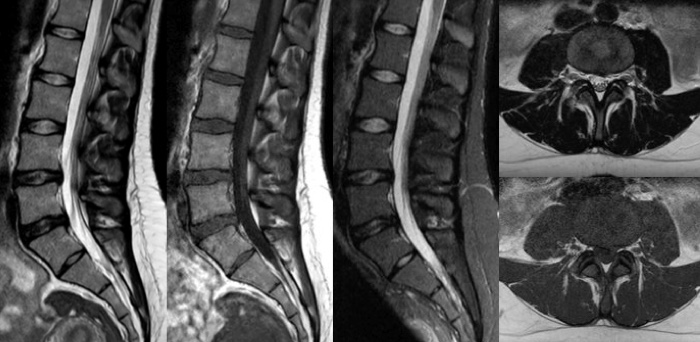

Gagnez du temps grâce à Compressed SENSE qui permet de réduire la durée de l’examen d’imagerie jusqu’à 50 %2 avec une qualité d’image quasi-identique. Produisez des images IRM exceptionnelles avec une résolution supérieure de 60 % pour un diagnostic sûr.

Classique

Compressed SENSE